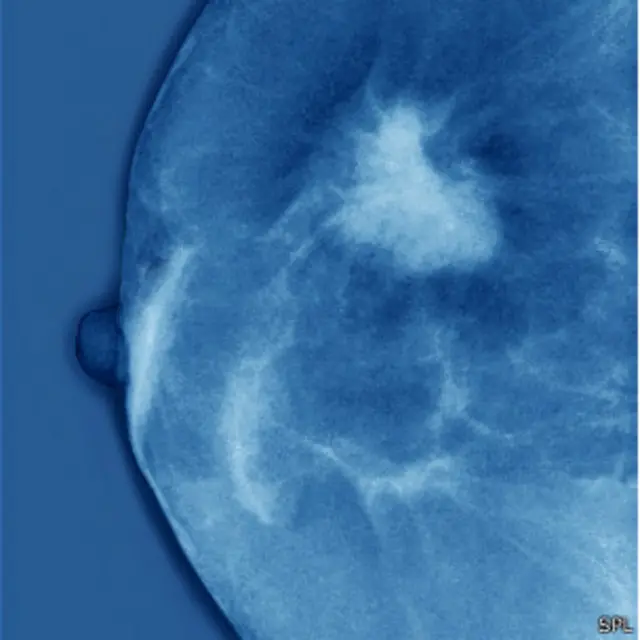

Em sua essência, o câncer é uma célula entre milhões de outras que começa a funcionar mal. No caso do câncer de mama, na maioria das vezes essa célula maligna fica nos ductos que levam o leite da glândula mamária até o mamilo. Mas, por que ali e não em outra parte? O que há nesta região?

Eles explicam que as células-mãe se dividem em células chamadas de diferenciadas ou finais, que, por sua vez formam o ducto mamário. E é nessas células em que se origina o câncer de mama, afirmam os especialistas.